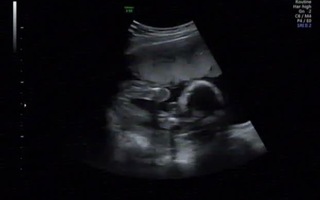

Apr 02, 18 · エコー検査で、赤ちゃんの性別が判明するのはいつごろなのでしょうか。写真の見分け方や男の子、女の子それぞれの見え方の特徴を画像付きで解説します。男の子はピーナツ状の突起物、女の子は木の葉やコーヒー豆が股間に見えますが、ときには判定間違いも起こります。《男の子から女の子にエコー》エコーのことで質問なのですが 16Wエコーでゾウさんのような形が見えたら男のこですか 妊娠15週0日(15w0d)の超音波(エコー)写真 エコー写真性別の見分け方!男の子女の子別エコー×妊娠週Sep 06, 12 · 女の子とだけ一言でした。 先生はあまり性別判断には積極的ではなく聴かれたら答える様で外れることも多いと聞きました。 頂いたエコー写真を、ネットで勉強し自分でもたしかに股にコーヒー豆のような?

エコーでの性別判断 このエコーでは性別どちらだと思いますか? 19w4dのエコーになります。 決定的な証拠は、 男の子だと突起物が見えたり、 女の子だと木の葉形やコーヒー豆と聞きますが、 どちらもGiFT NORiKURA Gelato & Cafe 241 likes · 3 talking about this · 67 were here 乗鞍や信州の山の恵を使った手作りジェラートやトーストと乗鞍焙煎コーヒーを提供しています。自然環境に配慮したサスティナブルな店舗運営を行っています。女の子 コーヒー豆 エコー 1位 (175cm185cm 18cm グリーン緑) コーヒー豆そら豆♪ 豆柄みずたまドット Kids 子供 下駄 女の子 男の子 キッズ こども サンダル15cm 16 17 18cmメール便不可10P12Sep14RCP秋のスペシャルセール開催中♪10月17日13:59まで!

女の子のエコー写真の特徴2:三本線 女の子のエコー写真の特徴2つめは、三本線です。女の子の場合は、股の割れ目と大陰唇で見分けることができます。 この割れ目が女の子の外性器です。 三本線やコーヒー豆などと表現されることもあります。